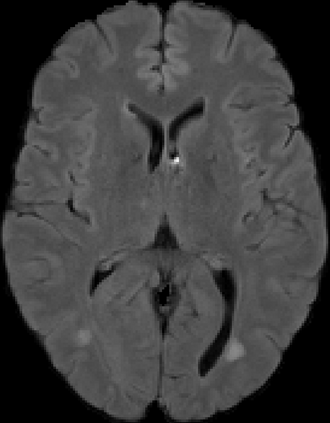

Assessment of lesions and their longitudinal progression from brain magnetic resonance (MR) images plays a crucial role in diagnosing and monitoring multiple sclerosis (MS). Machine learning models have demonstrated a great potential for automated MS lesion segmentation. Training such models typically requires large-scale high-quality datasets that are consistently annotated. However, MS imaging datasets are often small, segregated across multiple sites, with different formats (cross-sectional or longitudinal), and diverse annotation styles. This poses a significant challenge to train a unified MS lesion segmentation model. To tackle this challenge, we present SegHeD, a novel multi-dataset multi-task segmentation model that can incorporate heterogeneous data as input and perform all-lesion, new-lesion, as well as vanishing-lesion segmentation. Furthermore, we account for domain knowledge about MS lesions, incorporating longitudinal, spatial, and volumetric constraints into the segmentation model. SegHeD is assessed on five MS datasets and achieves a high performance in all, new, and vanishing-lesion segmentation, outperforming several state-of-the-art methods in this field.